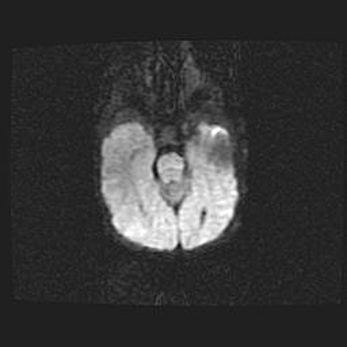

Сообщающаяся гидроцефалия. Кистозная энцефаломаляция головного мозга.

Возраст: 3 месяца 4 дня

Вес: 3100 г

Пол: женский

Окружность головы: 34 см

Срок гестации: 31 неделя

Кистозная энцефаломаляция головного мозга - одна из форм поражения головного мозга в детском возрасте. Характеризуется возникновением множественных и распространённых кист в коре, белом веществе и подкорковых образованиях головного мозга у плодов, новорождённых и детей раннего возраста. Развитие кистозной энцефаломаляции связано с внутриутробной асфиксией и гипотонией, родовой травмой, тромбозом синусов, пороками развития сосудов, инфекциями, сепсисом и другими причинами. Наиболее значимые инфекционные агенты: вирусы простого герпеса, цитомегалии, краснухи, токсоплазмы, энтеробактерии, золотистый стафилококк и другие.